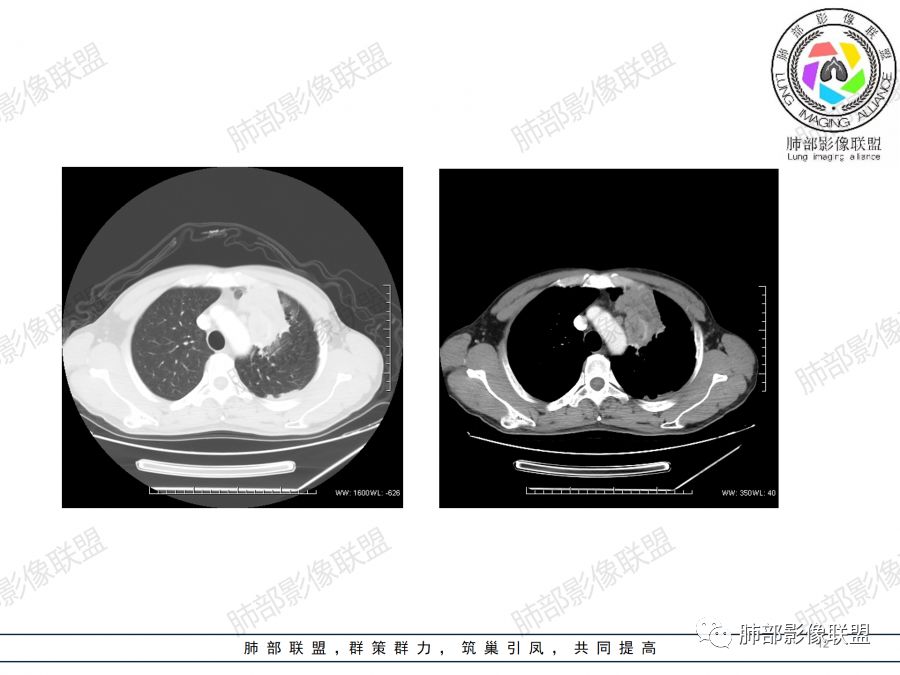

病例小结(跟着南大套路)

1.左肺上叶尖后段体积变化不大,病灶长轴沿支气管血管束向肺门侧生长,

2.病灶外围大,内带小,外朝内蔓延

3.病灶边缘以收缩为主,局部稍膨隆,

4.病灶整体轻中度强化,强化较均匀,局部见多个管状低密度影,边界清,考虑支气管粘液栓;病灶局部可小灶样的低密度区,未见强化,考虑坏死灶,坏死灶周围见明显强化的壁,壁清楚、光整,未见中断,倾向炎性肉芽肿的坏死;

5.病灶内血管部分走形自然,部分走形僵直、粗细不均,提示病灶有部分破坏力,但是不强;

6.病灶与纵隔胸膜呈“糊墙”样改变,倾向炎性病灶;

6.纵隔淋巴结肿大,密度均匀,强化均匀;

综合分析

本病例未行冠矢状位重建,未提供连续薄层图像,病灶与支气管情况呈现不满意。

1.中年男性,慢性病程,以咳嗽咳痰为主;

2.双上肺多发病灶,左肺上叶病灶沿血管支气管束分布,由外朝内,以平直收缩为主,周围有斑片渗出,胸膜糊墙,支持炎性病灶或是伴有肿瘤灶可能性。

两上肺发病,多支持结核等感染,但结核基础上伴发肺癌并不鲜见!

3.病灶内多支支气管粘液栓,炎性及恶性均可,但是炎性多于恶性;强化杂乱不均,病灶内小灶坏死比规则,支持炎性肉芽肿病变。

鳞癌病灶如较大,强化常不够显著且多见相对大范围湖泊样坏死。

4. 应仔细观察病变的支气管情况,如果支气管出现腔内结节或阻塞征象,需要提示临床干预,用支气管镜、穿刺等手段来进一步确诊。

5.  本例的焦点主要集中在结核与周围型肺鳞癌的鉴别诊断上!

病灶与大气道的关系未能满意呈现,但如此大范围病灶紧贴胸膜却未见胸壁纵隔组织结构侵犯破坏是不大符合肺鳞癌的生物学行为的。